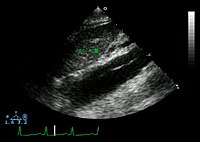

The transesophageal echocardiogram (TEE) is a good test in the diagnosis of aortic dissection, with a sensitivity up to 98% and a specificity up to 97%. It has become the preferred imaging modality for suspected aortic dissection. It is a relatively noninvasive test, requiring the individual to swallow the echocardiography probe. It is especially good in the evaluation of AI in the setting of ascending aortic dissection, and to determine whether the ostia (origins) of the coronary arteries are involved. While many institutions give sedation during transesophageal echocardiography for added patient comfort, it can be performed in cooperative individuals without the use of sedation. Disadvantages of TEE include the inability to visualize the distal ascending aorta (the beginning of the aortic arch), and the descending abdominal aorta that lies below the stomach. A TEE may be technically difficult to perform in individuals with esophageal strictures or varices.

Aortic dissection with an intramural hematoma as seen on TEE

Type A aortic dissection[23]